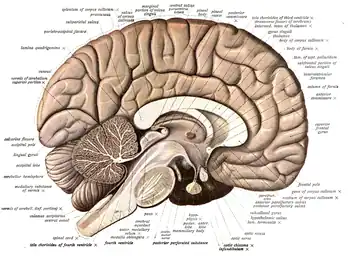

The cerebrum, the largest part of the human brain, consists of two cerebral hemispheres. Each hemisphere has an inner core composed of white matter, and an outer surface – the cerebral cortex – composed of grey matter. The cortex has an outer layer, the neocortex, and an inner allocortex. The neocortex is made up of six neuronal layers, while the allocortex has three or four. Each hemisphere is conventionally divided into four lobes – the frontal, temporal, parietal, and occipital lobes. The frontal lobe is associated with executive functions including self-control, planning, reasoning, and abstract thought, while the occipital lobe is dedicated to vision. Within each lobe, cortical areas are associated with specific functions, such as the sensory, motor and association regions. Although the left and right hemispheres are broadly similar in shape and function, some functions are associated with one side, such as language in the left and visual-spatial ability in the right. The hemispheres are connected by commissural nerve tracts, the largest being the corpus callosum.

The cerebrum is connected by the brainstem to the spinal cord. The brainstem consists of the midbrain, the pons, and the medulla oblongata. The cerebellum is connected to the brainstem by three pairs of nerve tracts called cerebellar peduncles. Within the cerebrum is the ventricular system, consisting of four interconnected ventricles in which cerebrospinal fluid is produced and circulated. Underneath the cerebral cortex are several important structures, including the thalamus, the epithalamus, the pineal gland, the hypothalamus, the pituitary gland, and the subthalamus; the limbic structures, including the amygdalae and the hippocampi, the claustrum, the various nuclei of the basal ganglia, the basal forebrain structures, and the three circumventricular organs. Brain structures that are not on the midplane exist in pairs, so there are for example two hippocampi and two amygdalae. The cells of the brain include neurons and supportive glial cells. There are more than 86 billion neurons in the brain, and a more or less equal number of other cells. Brain activity is made possible by the interconnections of neurons and their release of neurotransmitters in response to nerve impulses. Neurons connect to form neural pathways, neural circuits, and elaborate network systems. The whole circuitry is driven by the process of neurotransmission.

The cerebrum, consisting of the cerebral hemispheres, forms the largest part of the brain and overlies the other brain structures.[7] The outer region of the hemispheres, the cerebral cortex, is grey matter, consisting of cortical layers of neurons. Each hemisphere is divided into four main lobes – the frontal lobe, parietal lobe, temporal lobe, and occipital lobe.[8] Three other lobes are included by some sources which are a central lobe, a limbic lobe, and an insular lobe.[9] The central lobe comprises the precentral gyrus and the postcentral gyrus and is included since it forms a distinct functional role.[9][10]

The brainstem, resembling a stalk, attaches to and leaves the cerebrum at the start of the midbrain area. The brainstem includes the midbrain, the pons, and the medulla oblongata. Behind the brainstem is the cerebellum (Latin: little brain).[7]

The cerebrum, brainstem, cerebellum, and spinal cord are covered by four[11] membranes called meninges. The membranes are the tough dura mater; the middle arachnoid mater and the more delicate inner pia mater. Between the arachnoid mater and the pia mater is the subarachnoid space and subarachnoid cisterns, which contain the cerebrospinal fluid.[12] The outermost membrane of the cerebral cortex is the basement membrane of the pia mater called the glia limitans and is an important part of the blood–brain barrier.[13] The living brain is very soft, having a gel-like consistency similar to soft tofu.[14] The cortical layers of neurons constitute much of the cerebral grey matter, while the deeper subcortical regions of myelinated axons, make up the white matter.[7] The white matter of the brain makes up about half of the total brain volume.[15]

Cerebrum

The cerebrum is the largest part of the brain and is divided into nearly symmetrical left and right hemispheres by a deep groove, the longitudinal fissure.[16] Asymmetry between the lobes is noted as a petalia.[17] The hemispheres are connected by five commissures that span the longitudinal fissure, the largest of these is the corpus callosum.[7] Each hemisphere is conventionally divided into four main lobes; the frontal lobe, parietal lobe, temporal lobe, and occipital lobe, named according to the skull bones that overlie them.[8] Each lobe is associated with one or two specialised functions though there is some functional overlap between them.[18] The surface of the brain is folded into ridges (gyri) and grooves (sulci), many of which are named, usually according to their position, such as the frontal gyrus of the frontal lobe or the central sulcus separating the central regions of the hemispheres. There are many small variations in the secondary and tertiary folds.[19]

The outer part of the cerebrum is the cerebral cortex, made up of grey matter arranged in layers. It is 2 to 4 millimetres (0.079 to 0.157 in) thick, and deeply folded to give a convoluted appearance.[20] Beneath the cortex is the cerebral white matter. The largest part of the cerebral cortex is the neocortex, which has six neuronal layers. The rest of the cortex is of allocortex, which has three or four layers.[7]

The cortex is mapped by divisions into about fifty different functional areas known as Brodmann's areas. These areas are distinctly different when seen under a microscope.[21] The cortex is divided into two main functional areas – a motor cortex and a sensory cortex.[22] The primary motor cortex, which sends axons down to motor neurons in the brainstem and spinal cord, occupies the rear portion of the frontal lobe, directly in front of the somatosensory area. The primary sensory areas receive signals from the sensory nerves and tracts by way of relay nuclei in the thalamus. Primary sensory areas include the visual cortex of the occipital lobe, the auditory cortex in parts of the temporal lobe and insular cortex, and the somatosensory cortex in the parietal lobe. The remaining parts of the cortex are called the association areas. These areas receive input from the sensory areas and lower parts of the brain and are involved in the complex cognitive processes of perception, thought, and decision-making.[23] The main functions of the frontal lobe are to control attention, abstract thinking, behaviour, problem-solving tasks, and physical reactions and personality.[24][25] The occipital lobe is the smallest lobe; its main functions are visual reception, visual-spatial processing, movement, and colour recognition.[24][25] There is a smaller occipital lobule in the lobe known as the cuneus. The temporal lobe controls auditory and visual memories, language, and some hearing and speech.[24]

The cerebrum contains the ventricles where the cerebrospinal fluid is produced and circulated. Below the corpus callosum is the septum pellucidum, a membrane that separates the lateral ventricles. Beneath the lateral ventricles is the thalamus and to the front and below is the hypothalamus. The hypothalamus leads on to the pituitary gland. At the back of the thalamus is the brainstem.[26]